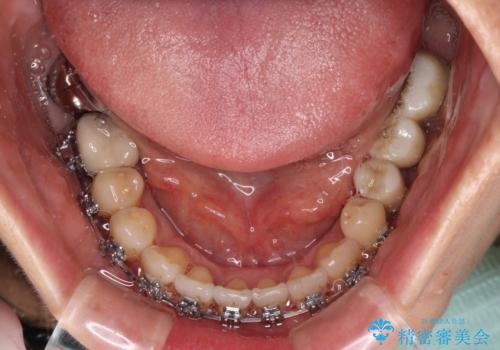

- 飛び出した上顎前歯と正中のズレを気にして来院された患者様です。

上顎正中が右側にずれていたので、むし歯が酷く抜歯が必要な左側臼歯を抜歯して正中を改善することとしました。

左下には新しいセラミックのブリッジが装着されていたため、ブリッジを壊さずに改善できるところまで咬み合わせを改善していくこととしました。

右上小臼歯は銀歯が装着されており、ワイヤー矯正の装置が装着できないため、事前に仮歯に変えてから矯正治療を行い、その後オールセラミッククラウンにて補綴治療を行いました。